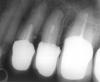

Hermit Опубликовано 28 октября, 2007 Поделиться Опубликовано 28 октября, 2007 После устновки коронок стали болеть многие зубы, которые врач посчитал возможным неперелечивать. В частности, верхняя пятерка. Нашел другого врача, который взялся за его лечение. Он считает, что следует после вскрытия канала обработать его и положить в него на три-четыре дня каласепт, а затем пломбировать гуттаперчивыми штифтами - после этого зуб будет уже готов для установки в него вкладки. Но достаточно ли такого короткого срока для излечения зуба и не рисковано ли так быстро ставить в него вкладку? Насколько состоятельны соседние 4 и 6 зубы? Что с ними следует сделать? Ссылка на комментарий

NataLee Опубликовано 28 октября, 2007 Поделиться Опубликовано 28 октября, 2007 После устновки коронок стали болеть многие зубы, которые врач посчитал возможным неперелечивать. В частности, верхняя пятерка. Нашел другого врача, который взялся за его лечение. Он считает, что следует после вскрытия канала обработать его и положить в него на три-четыре дня каласепт, а затем пломбировать гуттаперчивыми штифтами - после этого зуб будет уже готов для установки в него вкладки. Но достаточно ли такого короткого срока для излечения зуба и не рисковано ли так быстро ставить в него вкладку? Насколько состоятельны соседние 4 и 6 зубы? Что с ними следует сделать? Четвёрка только меня смущает... 5 и 6 можно попробовать перелечить. Если получится пройти каналы, то Каласепт я бы поставила на 1-2 недели. Хотя лично мне (но это именно лично мне ) больше нравятся пасты типа Витапекс. Их тоже имеет смысл ставить на 1-2 недели. Дольше держать их бесполезно, всё равно динамика (положительная или отрицательная) на снимках будет видна не ранее, чем через 6 месяцев. Поэтому каналы можно пломбировать и ставить вкладки, но всё это без гарантии. Ссылка на комментарий

NataLee Опубликовано 28 октября, 2007 Поделиться Опубликовано 28 октября, 2007 А чем смущает четверка? Ее депульпировали в районной поликлинике 2 года назад. Видимо плохо. Там же поставили затем криво штифт. Перед протезироваением старый штифт вытащили и поставивили новый. От старого штифта на зубе остался след - толи перфорация, толи внутренняя полость. Когда поставили коронки, зуб стал побаливать при нажатии на него сбоку со стороны языка, причем эта боль аналогична той, что держалась месяц-два после депульпации. Т.е. с образованием на стенке, видимым на снимке, она, возможно, не связана. Можно ли такой зуб перелечить и как? Меня вот и смушает эта деструкция костной ткани по дистальной стенке корня. Если это перфорация, такой зуб однозначно нельзя брать под протезирование. И сама возможность перелечивания под большим вопросом. Придут коллеги, пусть посмотрят, может, будет ещё какое-то мнение... И ортопедов не худо бы послушать Ссылка на комментарий

Hermit Опубликовано 28 октября, 2007 Автор Поделиться Опубликовано 28 октября, 2007 (изменено) Меня вот и смушает эта деструкция костной ткани по дистальной стенке корня. Если это перфорация, такой зуб однозначно нельзя брать под протезирование. И сама возможность перелечивания под большим вопросом. Придут коллеги, пусть посмотрят, может, будет ещё какое-то мнение... И ортопедов не худо бы послушать А как проверить, что это такое, ведь оно под десной? Надо вскрывать канал зуба и смотреть, на это "изнутри"? Помещаю еще три снимка четвертого зуба, сделанные перед протезированием. Изменено 28 октября, 2007 пользователем Hermit Ссылка на комментарий

Bier Опубликовано 28 октября, 2007 Поделиться Опубликовано 28 октября, 2007 Хермит, зачем вы обрезаете снимки? может мы еще что интересное разглядим? на мой взгляд, там была перфорация, которая никуда и не делась. Зуб весьма сомнительный для протезирования на мой взгляд. Ссылка на комментарий

NataLee Опубликовано 28 октября, 2007 Поделиться Опубликовано 28 октября, 2007 Хермит, зачем вы обрезаете снимки? может мы еще что интересное разглядим? на мой взгляд, там была перфорация, которая никуда и не делась. Зуб весьма сомнительный для протезирования на мой взгляд. Перфорация, однозначно Закрыта каким-то материалом. Может быть, имеет смысл перелечить и сделать хирургическое удлинение коронковой части (обнажить место этой перфорации)? Где ортопеды? Ссылка на комментарий

Doc Опубликовано 28 октября, 2007 Поделиться Опубликовано 28 октября, 2007 Перфорация, однозначно Закрыта каким-то материалом. Может быть, имеет смысл перелечить и сделать хирургическое удлинение коронковой части (обнажить место этой перфорации)? Где ортопеды? Ортопеды остыпались после тяжелой недели. Перфорация там серьезная. Под нагрузку зуб крайне ненадежен. Под одиночку с подпиской об отсутствии гарантии можно взять, но это будут эксперименты на живых людях. Лучше не рисковать, мне кажется. Хотя видал я такие перфорации, которые стояли и три и пять лет. Но больше вряд ли. Ссылка на комментарий